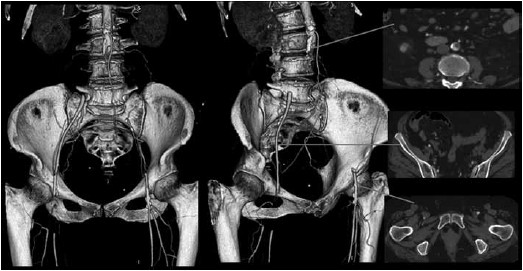

A paciente da questão anterior é submetida a uma angiotomografia de Aorta e ilíacas, sendo a reconstrução arterial 3D e cortes axiais selecionados apresentados a seguir.

Diante do quadro clínico e achado do exame de imagem, assinale a alternativa que corresponde respectivamente à principal hipótese diagnóstica e à conduta terapêutica.

Uma paciente de 65 anos, tabagista 35 anos/maço, obesa e portadora de hipertensão arterial sistêmica é admitida no Pronto Atendimento por queixa de dor de início súbito em membros inferiores, associada a impotência funcional dos membros e queda da própria altura. Seu exame físico demonstra ausência de pulsos desde a artéria femoral, associado a gradiente térmico dos pés. Há parestesia de artelhos e déficit motor à dorsiflexão dos pés. Ademais, ao Doppler de ondas contínuas não há fluxo arterial nas artérias podálicas.

A classificação Rutherford atribuída a esse quadro clínico é: